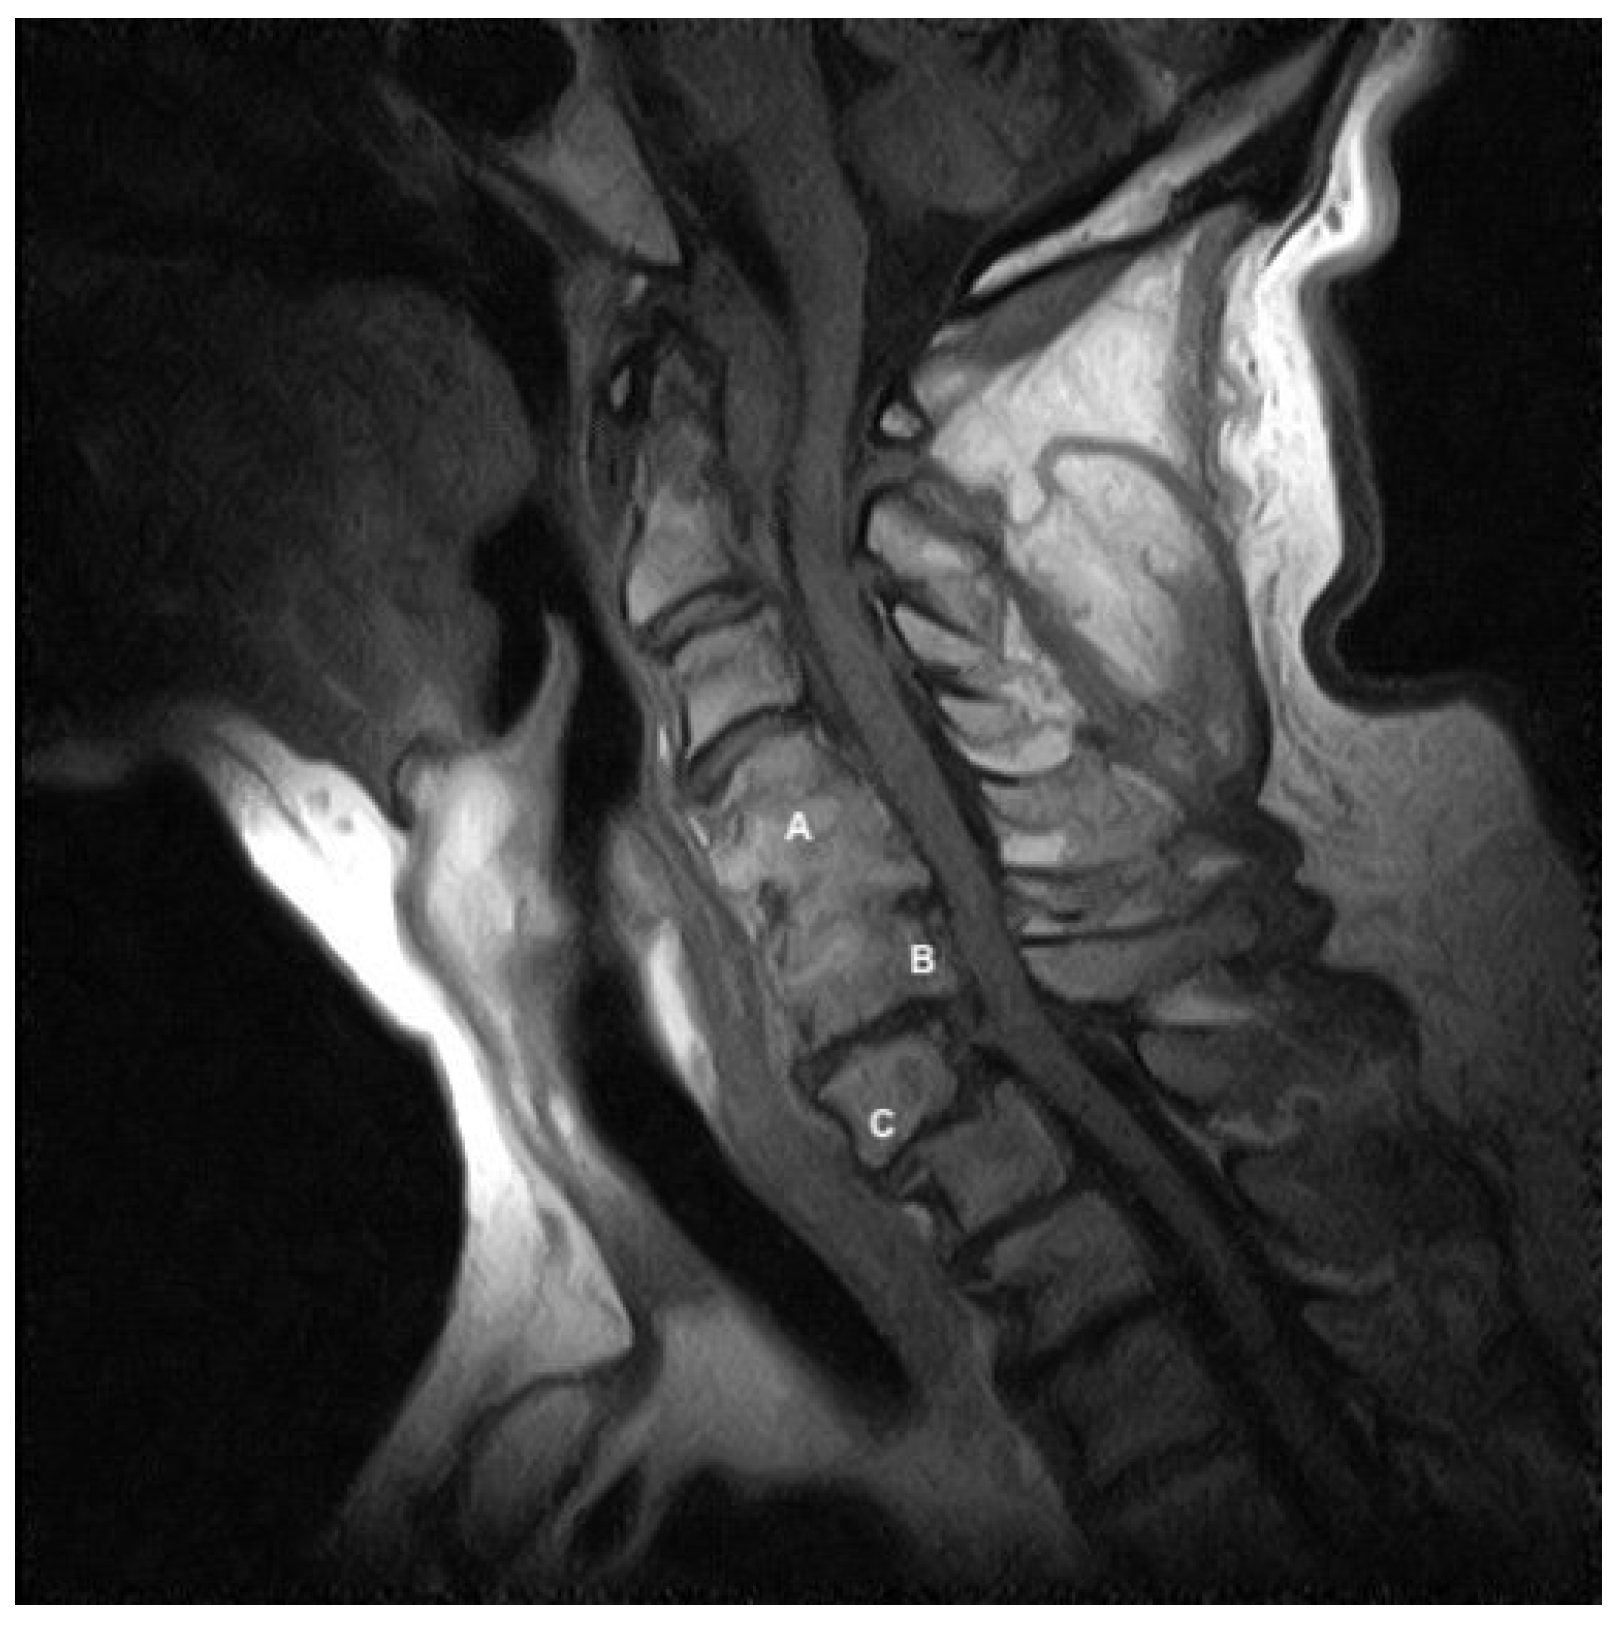

2. Case Presentation